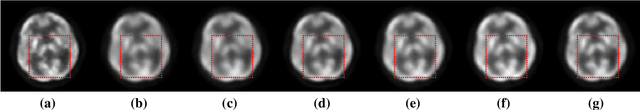

Abstract:Positron emission tomography (PET) is widely used in clinical practice. However, the potential risk of PET-associated radiation dose to patients needs to be minimized. With reduction of the radiation dose, the resultant images may suffer from noise and artifacts which compromises the diagnostic performance. In this paper, we propose a parameter-constrained generative adversarial network with Wasserstein distance and perceptual loss (PC-WGAN) for low-dose PET image denoising. This method makes two main contributions: 1) a PC-WGAN framework is designed to denoise low-dose PET images without compromising structural details; and 2) a transfer learning strategy is developed to train PC-WGAN with parameters being constrained, which has major merits; namely, making the training process of PC-WGAN efficient and improving the quality of denoised images. The experimental results on clinical data show that the proposed network can suppress image noise more effectively while preserving better image fidelity than three selected state-of-the-art methods.